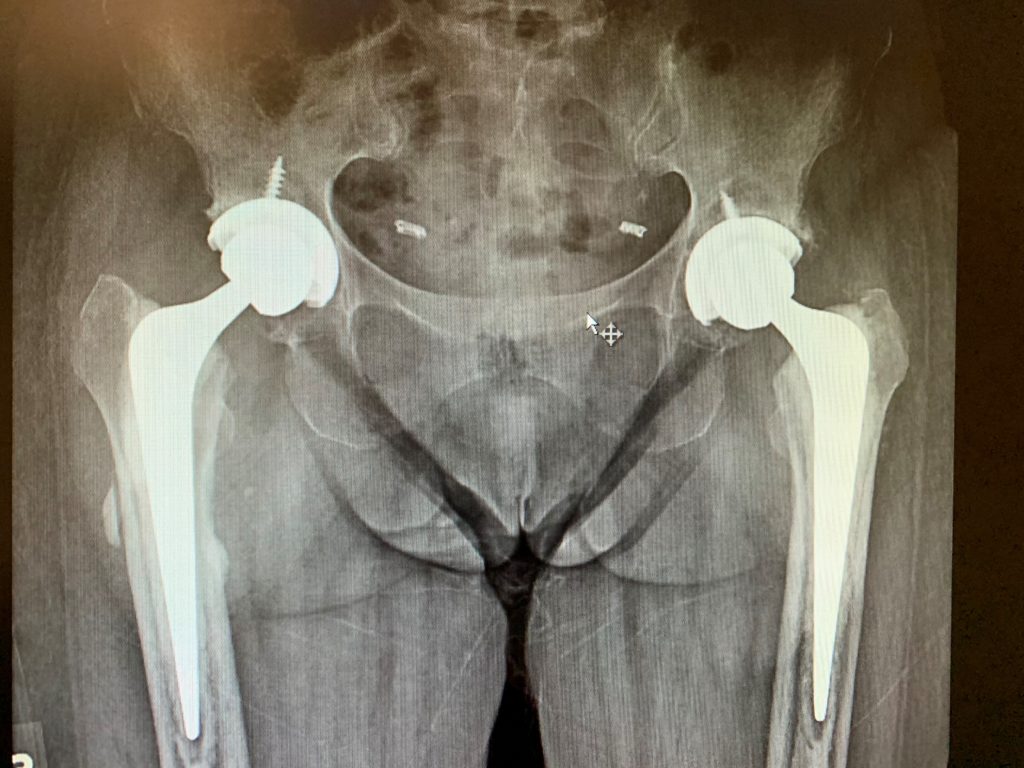

Case Study Bilateral hip replacement in 66 year old female Complete Hip Replacement New York there are 756 doctors in new york that treat hip replacement. dr roy davidovitch at orthopedic hip surgeons of nyc in new york, ny specializes in minimally invasive orthopedic hip surgery, total hip. designed for durability, a replaced hip can last for as long as twenty years. We also specialize in minimally invasive, single. hss is. Hip Replacement New York.